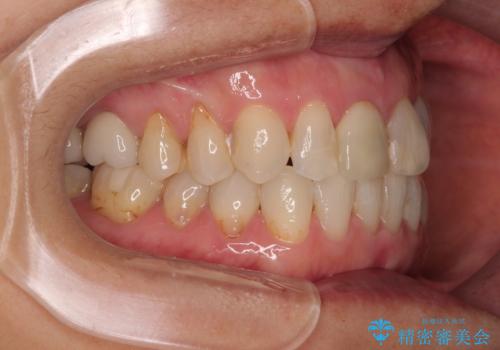

デコボコと銀歯 矯正治療とセラミック治療で綺麗な口元に

- 前歯のデコボコと口を開けたときに見える銀歯を気にして来院された患者様です。

矯正治療後に銀歯をセラミッククラウンなどに置き換えていくと、どうしても後戻りを起こしてしまうため、矯正治療が概ね終了した時点で銀歯を全てセラミックとし、最後に仕上げでインビザラインにを用いて細かいデコボコを改善していくこととしました。

とても明るい口元となり、人目を気にせず、大きく口を開けて笑えるようになりました。